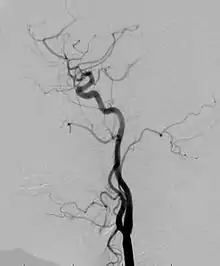

Angiogram: an angiogram can also be ordered to get a detailed look at the blood vessels in the affected or overgrown limb. In this test a physician injects a dye into the blood vessels that will help see how the blood vessels are malformed.[23]